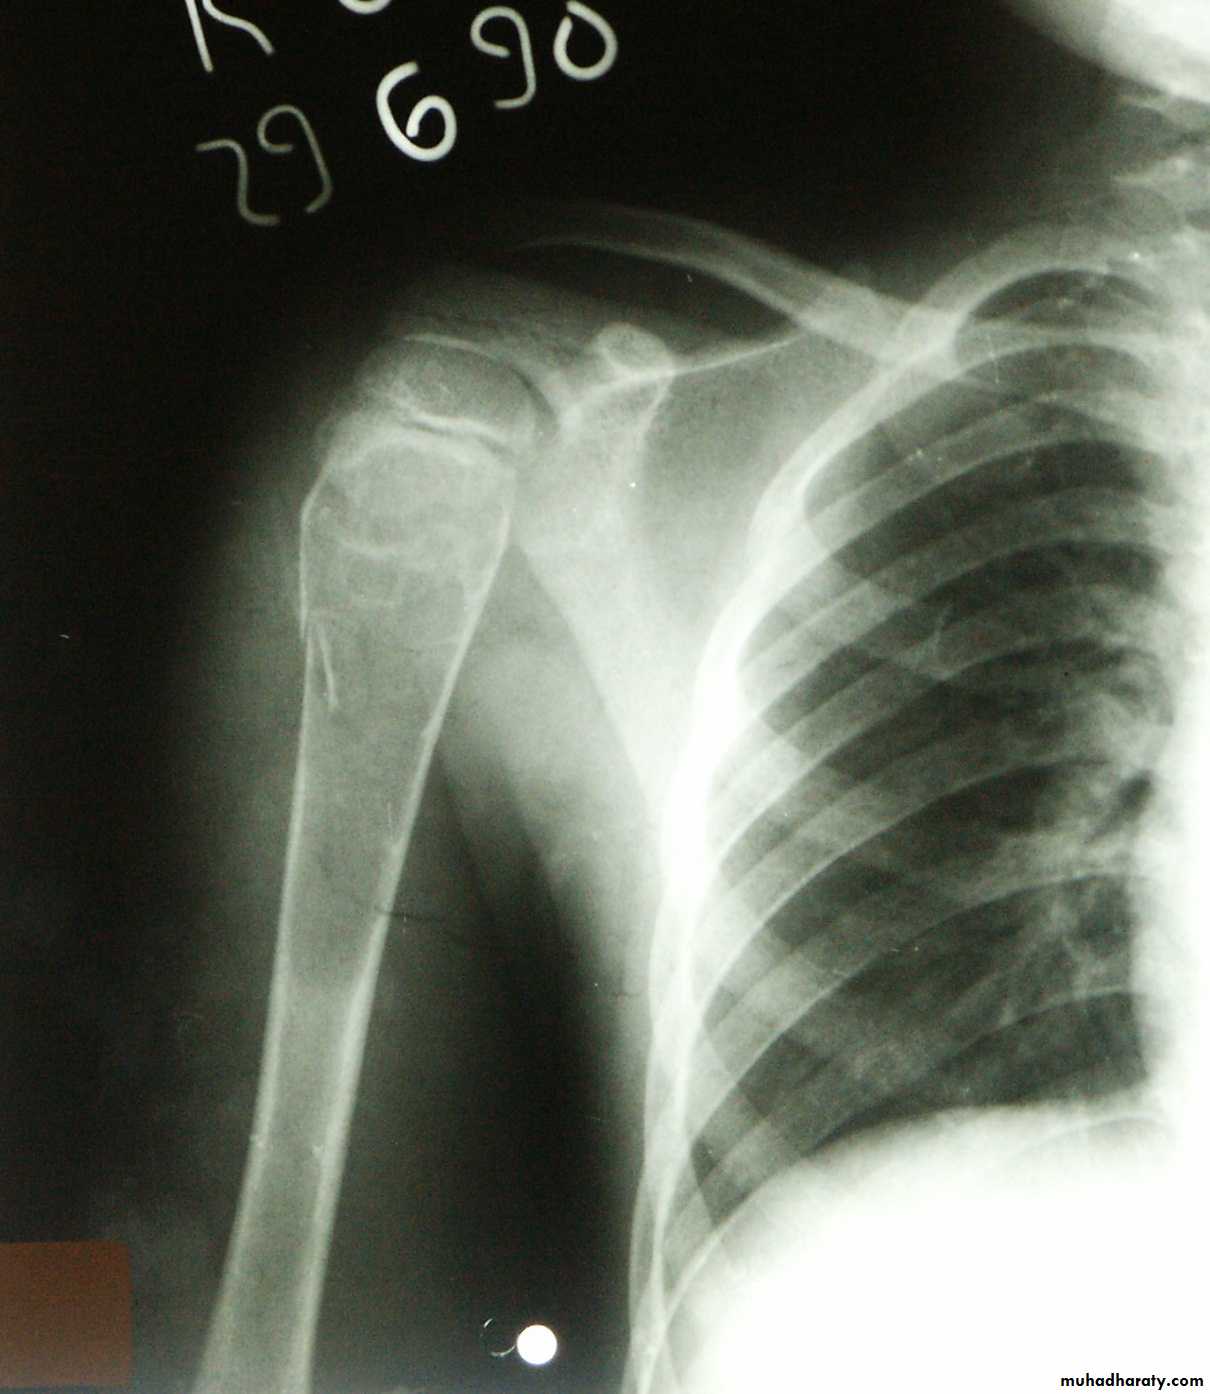

highly malignant tumour arising within the bone andspreading rapidly outwards to the periosteum and surrounding soft tissues. It is said to occur predominantly

in children and adolescents, 10-25 years

may affect any bone but most commonly involves the

long-bone metaphysis, especially around the knee andat the proximal end of the humerus.

X-rays

variable hazy osteolytic .

areas may alternate with unusually dense Osteoblastic areas.The endosteal margin is poorly defined. often

The cortex is breached .

The tumour extends into the adjacent tissues; when this happens.

Streaks of new bone appear, radiating outwards from the cortex – the so-called ‘sunburst’ effect.Reactive new bone forms at the angles of periosteal elevation (Codman’s triangle).